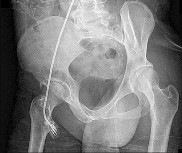

Question 1:

A 25-year-old male sustains a high-energy Pauwels type III femoral neck fracture. In a young adult with this vertical fracture pattern, which of the following internal fixation constructs biomechanically offers the greatest resistance to vertical shear forces and varus collapse?

Options:

- Three parallel partially threaded cancellous screws

- Sliding hip screw with a supplemental derotational screw

- Dynamic condylar screw

- Cephalomedullary nail

- Three fully threaded cortical screws placed in a divergent pattern

Correct Answer: Sliding hip screw with a supplemental derotational screw

Explanation:

Pauwels type III femoral neck fractures have a vertical orientation (>50 degrees) and are subjected to high shear forces rather than compressive forces. Biomechanical studies have consistently demonstrated that a fixed-angle device, such as a sliding hip screw (SHS) with a supplemental derotational screw, provides superior stability against vertical shear and varus collapse compared to multiple cancellous screws in these specific high-angle fractures.